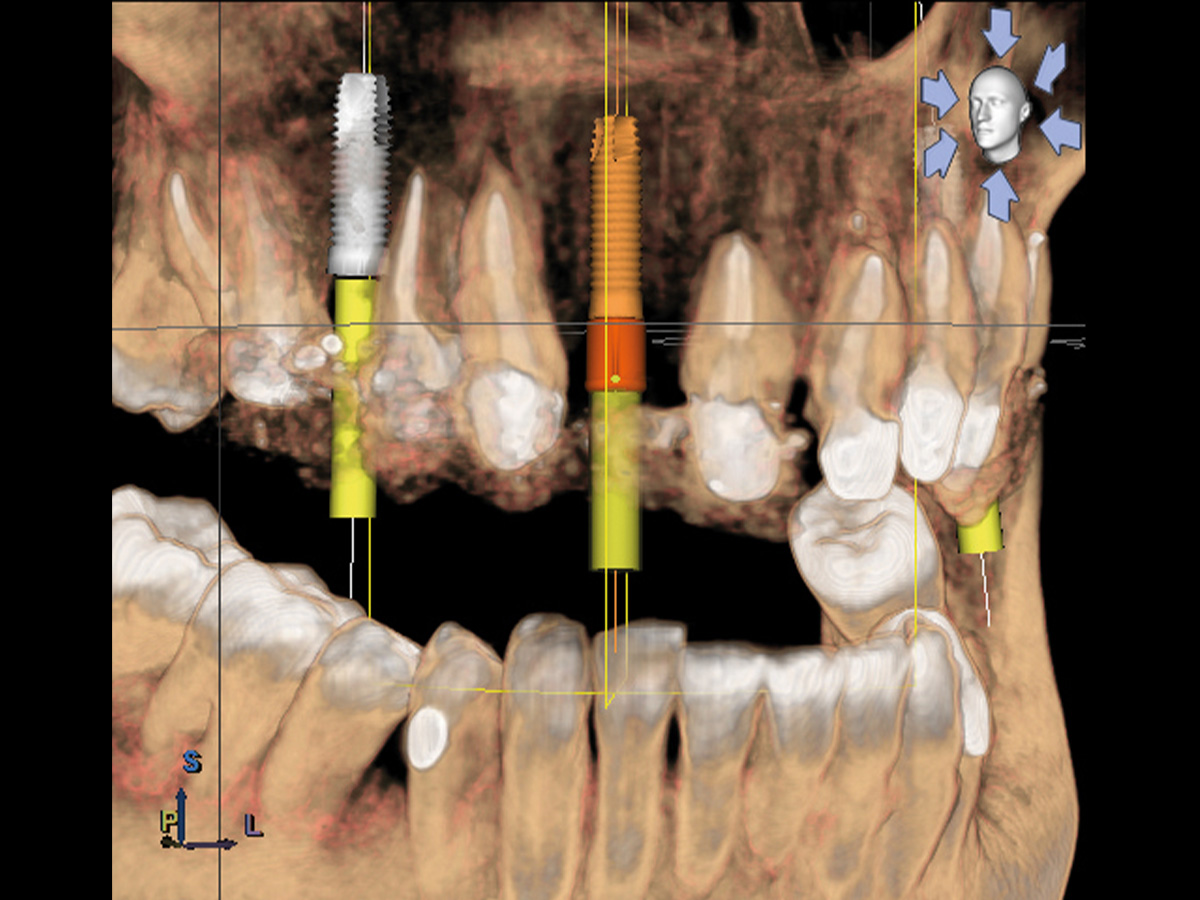

Abbildung 3

3D-Darstellung der geplanten Implantatposition.